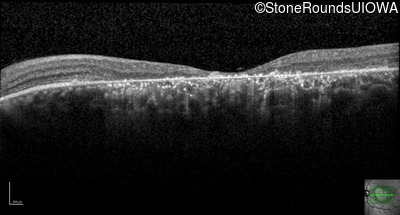

AR Stargardt Disease (IIA)

Age at visit: 35 years

This 35 year old woman first started holding her reading material closer than normal when she was 7 years old.

Diagnosis & molecular findings

AR Stargardt Disease ABCA4 Val1681 del15gctGTGGTTGCCATCTGC Gly1961Glu GGA>GAA AR